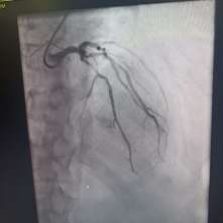

60 year old male known diabetic, hypertensive and dyslipidaemic presented with unstable angina, Coronary angiogram revealed Mid RCA pre crux lesion of 80-90% stenosis and PDA and PLV arising from Mid RCA (Fig 1). It was an angulated bend post bifurcation and hence Fielder FC wire support was taken to easily manipulate the vascular bifurcation (Fig 2) and successful PTCA+ stent to Mid RCA was done with 3x24mm Yukon choice flex stent (Fig 3& 4). TIMI III flow was achieved and post procedure period was uneventful.

FIG 3: Stent deployment